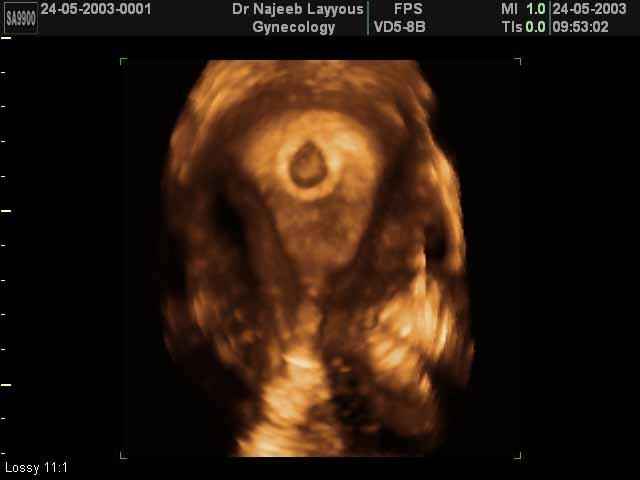

3D First Trimester Ultrasound Scan Photos